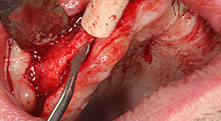

Is overheating of bone a factor to be considered with deep preparations?

Bratu: Yes, this problem cannot be disregarded. In other systems the coolant comes out of the handpiece or the instrument, but is relatively distant from the surgical site. In the hands of inexperienced clinicians overheating can result, particularly during deep cuts. In contrast, in the Piezomed the coolant outlet is close to the instrument tip. In my experience, this improves safety and gives better results.

Could you describe briefly, for example, your procedure for mobilizing bone blocks for transplantation?

Bratu: We prefer to harvest bone from the external oblique ridge of the posterior mandible, not from the interforaminal region. After the soft-tissue incision, we use the new saws to define the amount of bone to harvest. With this approach, we also use them for the entire preparation in almost 80% of cases. We may also use other piezo instruments and then at the end a chisel to mobilize the block. We find that this is a very effective surgical technique.